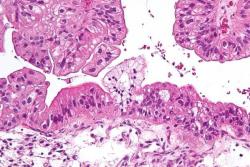

سرطان به معنای رشد، تکثیر و گاهی انتشار غیر طبیعی سلول های بدن است. تمامی سرطان ها نه تنها دارای الگوی رشد مهارگسیخته هستند بلکه تمایل به جدا شدن از منشا اصلی و متاستاز نیز دارند. اما مطالعات اخیر محققان انگلیسی دانشگاه لیدز ابعاد جدیدی از سرطان را بررسی می کند.

در این مطالعه که با محوریت سرطان تخمدان انجام شده بود، محققان دریافتند جهش های ژنتیکی تنها موردی نیستند که در سرطان باید مورد توجه قرار بگیرند بلکه عدم توازن در پروتئین های داخل سلولی نیز می تواند دلیلی برای بروز سرطان باشد. این کشف بزرگ می تواند راهگشای محققان باشد زیرا در انواع سرطان ها تنها اختلالات ژنتیکی مورد توجه قرار می گرفتند. عدم توازن پروتئینی می تواند راه حلی برای تشخیص و بررسی پاسخ مثبت یا منفی بدن بیمار به شیمی درمان یا چگونگی رشد و گسترش تومورها باشد.